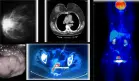

La progresión de los hallazgos radiológicos ofreció pistas diagnósticas retrospectivamente importantes:

Primera radiografía: Neumonía multifocal predominantemente izquierda

Segunda evaluación: Enfermedad intersticial bilateral con lesiones cavitarias en lóbulo superior izquierdo

TC de tórax: Confirmación de cavitación (característica de reactivación tuberculosa) y derrames pleural y pericárdico